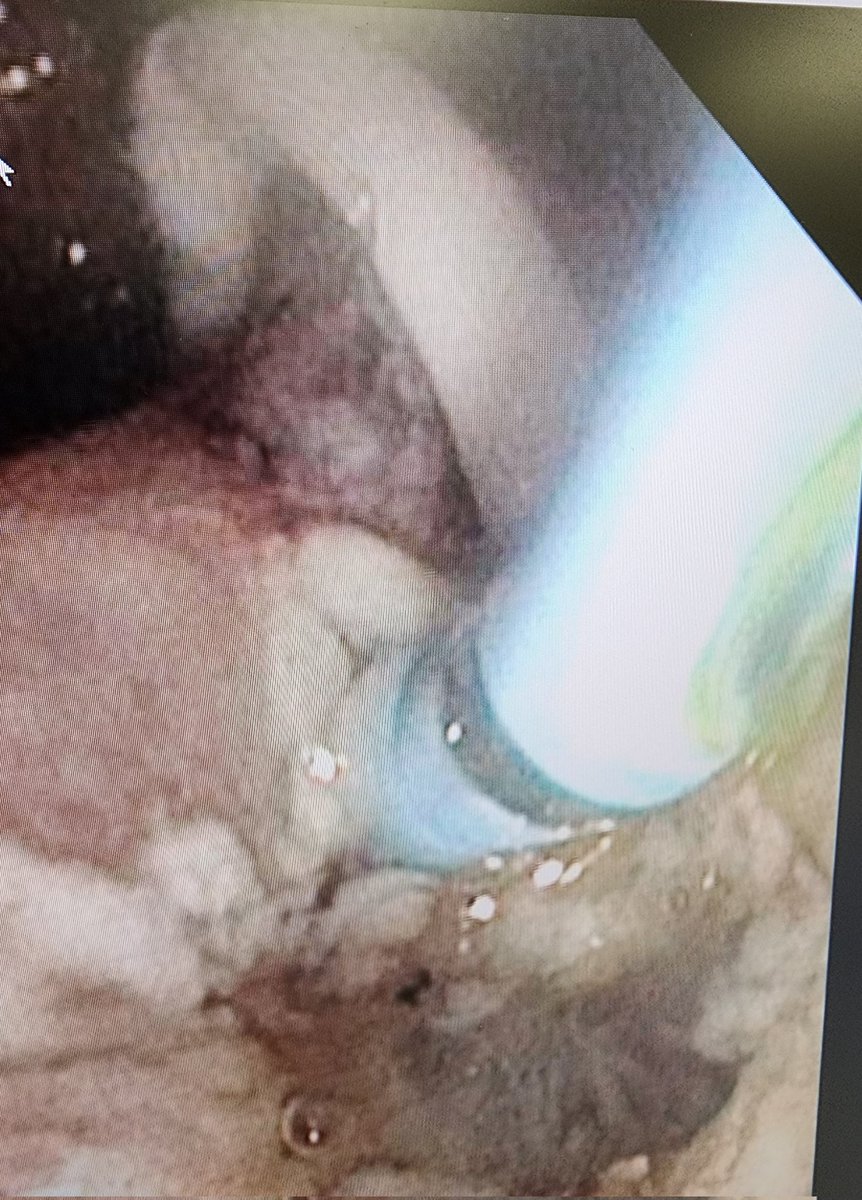

Only 1 and 1/2 months into fellowship and I got to do ampullectomy( pics below), liver biopsy, suturing, TIF, Stretta, Pancreatic endotherapy, needle knife fistulotomy and multiple native ERCPs with high quality EUS training. Great mentors. Advanced fellowship @ Geisinger